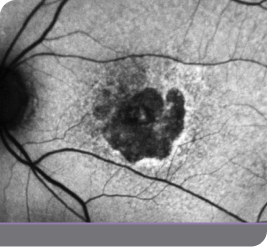

1y 1m

IZERVAY-treated right eye (OD)

Image of right eye treated with IZERVAY and untreated left eye at 1y 1m

Untreated left eye (OS)

OD=oculus dexter; OS=oculus sinister.

Images courtesy of Dr. Beth Richter.

This is an individual patient case study. It should be interpreted with caution and cannot be considered conclusive. Individual results may vary. In the GATHER trials, sham was used as the comparator.